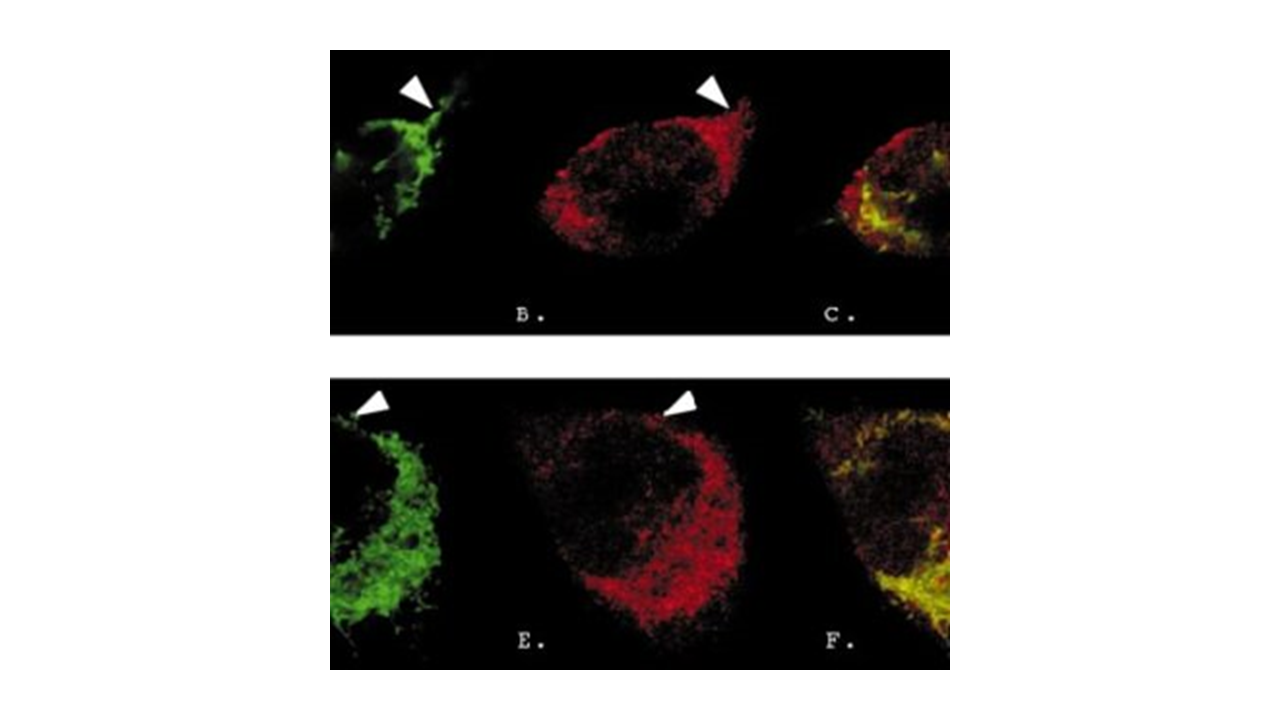

Methods: Transgenes encoding EGFP under NF-κB or STAT3 promoters were transfected into the C2C12 mouse myoblast cell line, along with ROSA26-CRISPR/Cas9 for gene integration at the Safe Harbor Site of the genome. Stable cell lines were obtained through cycles of G418 drug selection, fluorescence-activated cell sorting (FACS), and subcloning. EGFP expression was evaluated in response to oxidative stress (0.5mM H2O2) or burn-derived 10% serum (from day3 burn rats, 30% BSA) for 24 hours. Drug efficacy testing involved trehalose (autophagy/mitophagy modulator) and humanin (anti-inflammatory peptide, Alzheimer’s disease drug candidate).

Results: Both oxidative stress and burn-serum-induced stress increased EGFP expression by 1.4 to 2.6-fold in both NF-κB and STAT3 cell lines, demonstrating the versatility of our cell lines in measuring inflammatory responses. Trehalose and humanin effectively suppressed the inflammatory response.